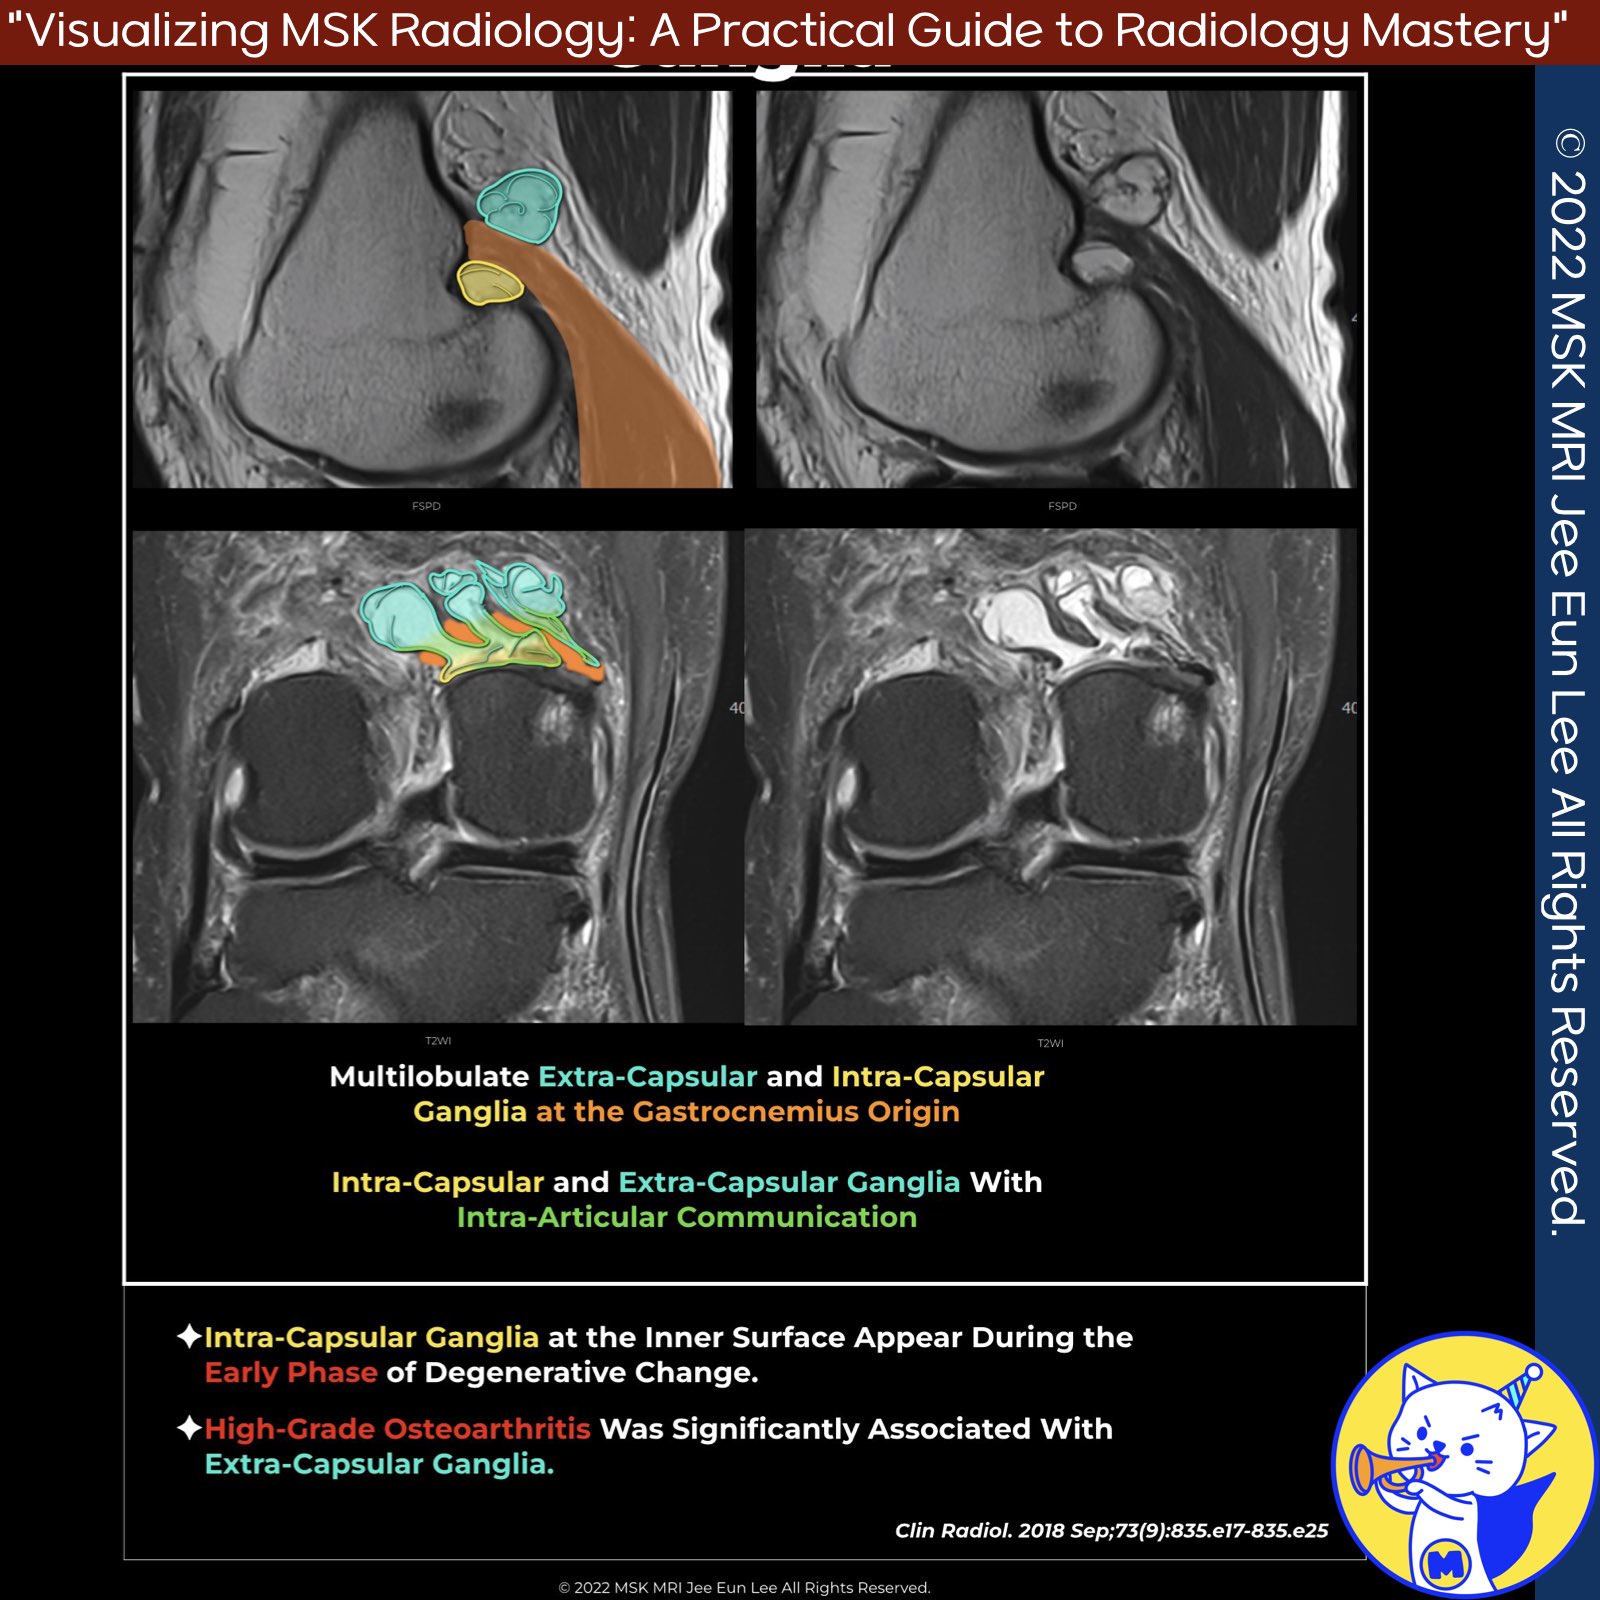

📌 Gastrocnemius Ganglia

- Gastrocnemius ganglia are cystic formations commonly found at the medial head of the gastrocnemius muscle.

- These ganglia are often multiseptated and can be detected through knee MRI.

✅ Extra-capsular ganglia at the gastrocnemius origin

- Extra-capsular ganglia at the gastrocnemius origin are frequently observed on knee MRI.

- They exhibit typical features of ganglia found at other sites. High-grade osteoarthritis has a significant association with the presence of extra-capsular ganglia.

✅ Classification of Ganglia

- Intra-capsular Ganglia: These cystic lesions protrude into the PCGU but remain confined to its most superficial margin.

- Extra-capsular Ganglia: These ganglia extend beyond the superficial margin of the PCGU.

✅ Developmental Stages of Ganglia

- Early Stage: A crescentic ganglion develops at the inner surface of the PCGU.

- Early-Intermediate Stage: The cyst within the intra-capsular location transforms into a rounded shape.

- Intermediate Stage: The rounded ganglion extends into the extra-capsular area.

- Intermediate-Late Stage: A multilobulate extra-capsular ganglion with internal septa and unclear intra-articular communication forms.

- Late Stage: The ganglion becomes encapsulated and remains extra-capsular, lacking intra-articular communication.